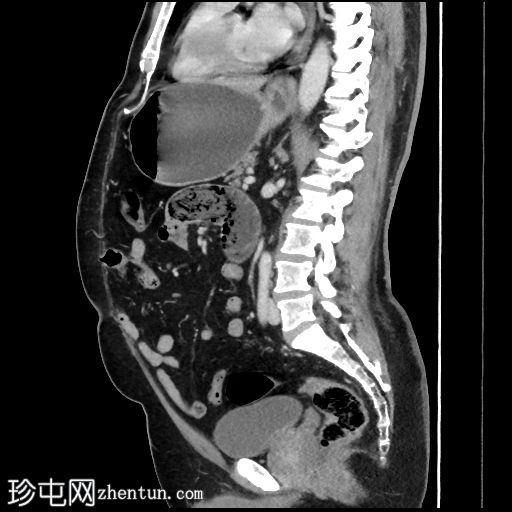

轴位增强扫描(门静脉期)

胃和十二指肠明显扩张,充满液体,直径约53毫米,可见斑驳状气体样肿块。

十二指肠第四段为移行区,其后为塌陷的空肠和回肠袢。

在CT扫描中,胃石引起的梗阻通常表现为边界清晰的管腔内肿块,在移行点处可见斑驳的气体或“粪便样”外观,并伴有近端肠管和胃扩张,因此CT是最准确的诊断方法。内镜下,植物性胃石通常质地较硬,由压实的食物和植物纤维组成,反映了慢性消化淤积和消化不良。